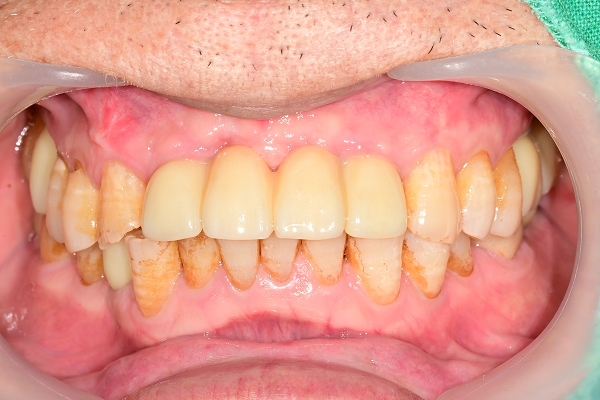

전악 케이스

- 상·하악 전체 보철 설계를 통해 정확한 교합(물림) 회복

- 심미·발음·저작 기능을 종합 고려한 자연스러운 전악 임플란트